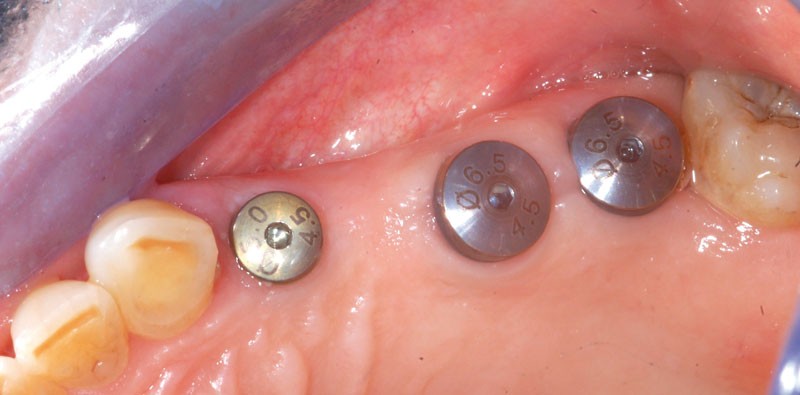

Une fois les transferts pick-up EV® transvissés, le porte-empreinte Tray, fenestré en regard des transferts, est chargé de matériau monophase Impregum™ Penta™ Soft (3M ESPE). Du matériau est déposé autour des transferts à l’aide d’une seringue. Après dévissage des transferts, ces derniers sont emportés dans l’empreinte et les analogues d’implants sont transvissés.